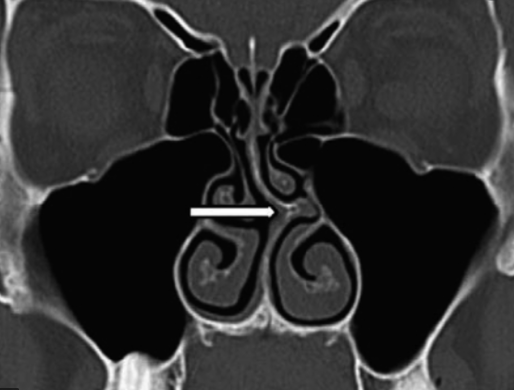

Sinusitis Our Ent Specialist Answers Your Questions